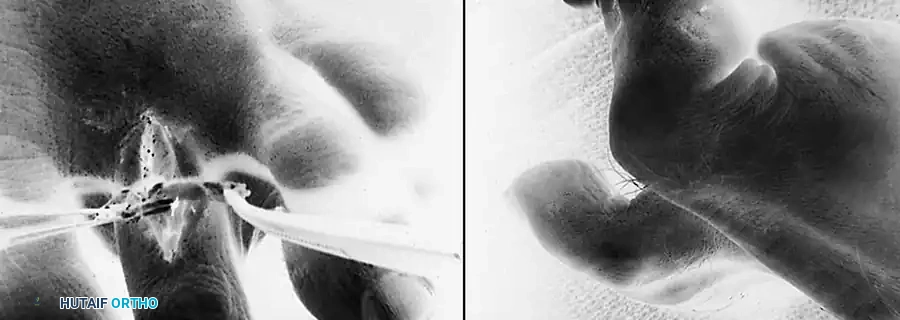

* If concurrent bony procedures (such as a Weil osteotomy or PIP arthrodesis) are performed, a smooth 0.045-inch Kirschner wire may be driven retrogradely across the PIP and MTP joints to maintain alignment during the initial healing phase.

- Weeks 0-3: The patient is placed in a rigid, flat-bottom postoperative shoe and allowed heel-weight-bearing only. The toe is maintained in a bulky compressive dressing, splinted in slight plantarflexion. If a K-wire was utilized, it remains in place.

- Weeks 3-4: The K-wire (if present) is removed in the clinic. The patient transitions to full weight-bearing in a stiff-soled shoe.